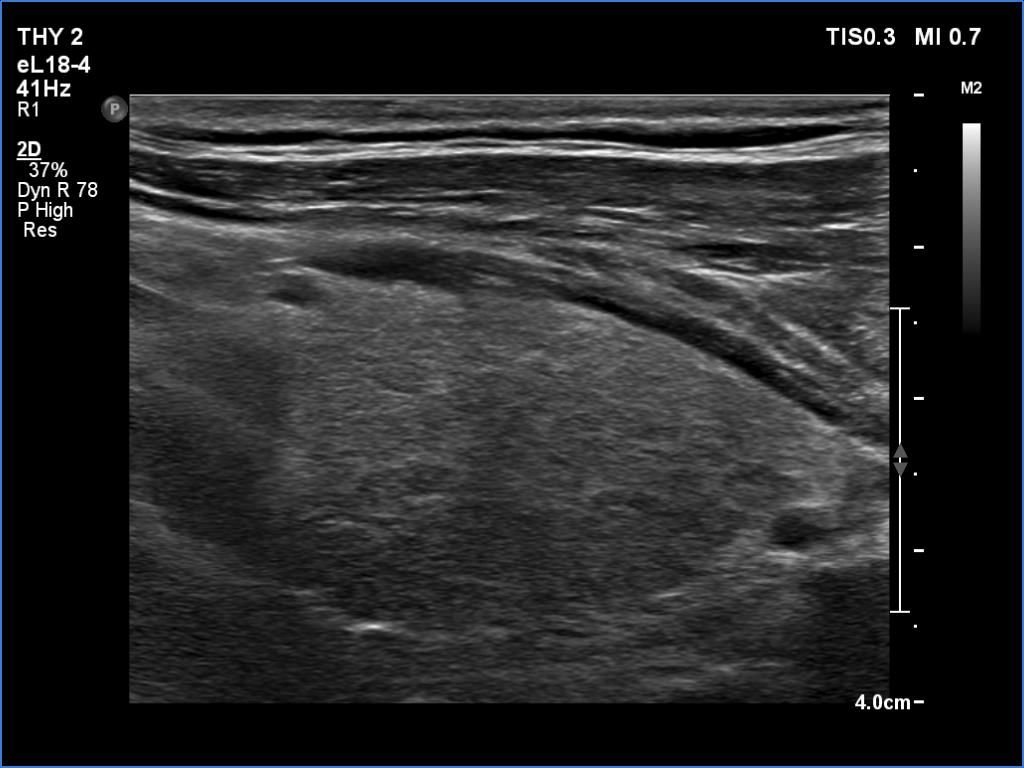

Ultrasonography. The right lobe was echonormal and intact. A large mass occupied almost the entire left lobe. On this side, normal thyroid tissue could only be identified in the dorsal part. The mass was composed of echonormal and hypoechoic areas, had macrocalcifications, irregular intranodular vascularity and proved to be very hard on elastography. There were multiple lymph nodes in III, IV and V left neck compartments. One of the nodes was in close proximity to the jugular vein and was suspicious of having broken into the vessel. The trachea was significantly narrowed at the lower level of the thyroid.

2. There are several remarkable findings in this case, e.g., the destruction of the left lobe by the tumor, the elastography pattern, the relation of the largest metastatic lymph node and the jugular vein, the ultrasound demonstration of the trachea' stricture.